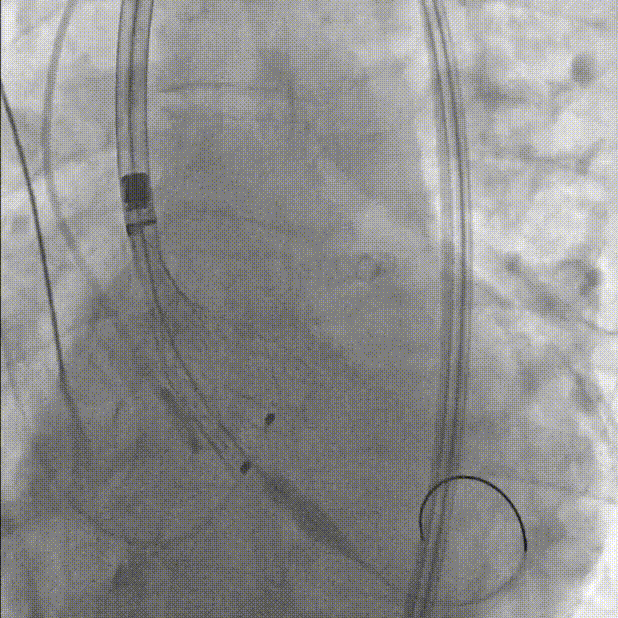

初始定位,左右窦重叠视图开始释放:

释放中期,快速起搏下释放到80%切换视图,并借助食管心超评估深度和反流情况:

完全释放和瓣膜脱钩:

术后导管测压压差为2mmHg:

最终根部造影:无反流,冠脉灌注良好: